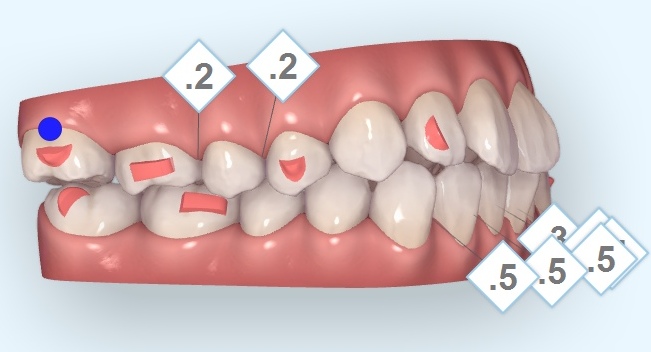

【インビザライン】矯正のために歯に隙間を作るIPRとは?その有用性を解説します!

こんにちは!大阪府羽曳野市 医療法人えみは会 加藤総合歯科・矯正歯科理事長 加藤直之です。 今回は、インビザライン矯正で高確率で必要

【インビザライン】アタッチメントって何のために着けるの?必要性について解説します

こんにちは!大阪府羽曳野市 医療法人えみは会 加藤総合歯科・矯正歯科理事長 加藤直之です。 今回は、インビザラインになくてはならない